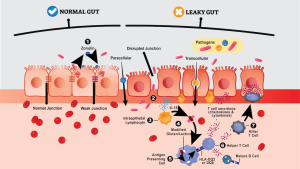

Leaky Gut Explained

Leaky Gut: What Is It and Is There a Cure? Dr. Steven Gundry Says Yes. Learn more about the signs of leaky gut, how it is at the root of most autoimmune diseases, and how it’s treated. What is leaky gut syndrome? It may surprise you to hear that disease